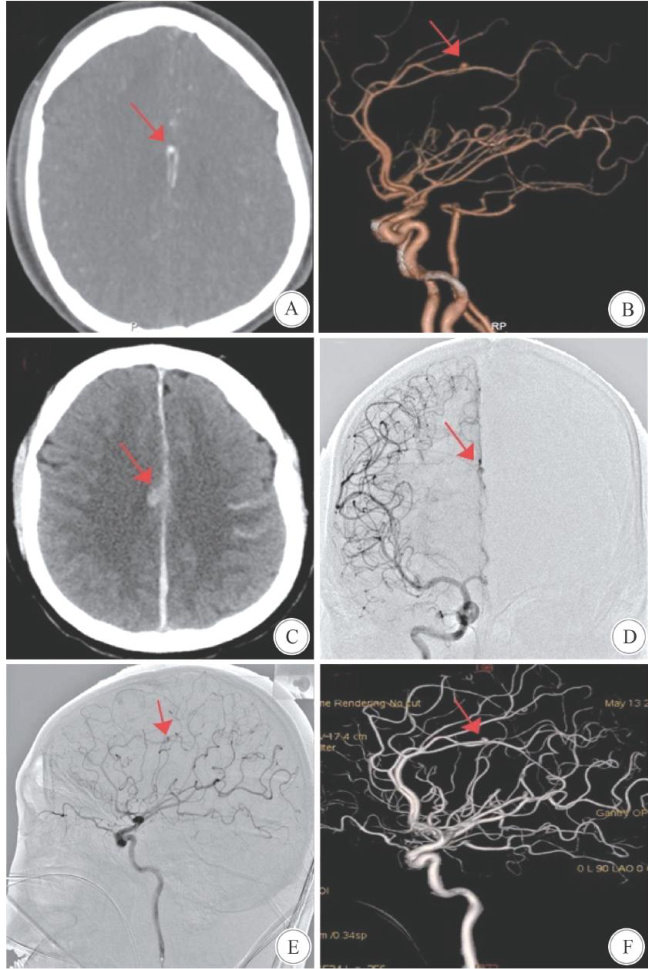

Abstract:ObjectiveTo analyze the diagnosisand treatment of a case of traumatic pericallosal aneurysm (TPA)caused by difuse axonal injury(DAI).MethodsThe clinical data of a patient with TPA secondary to DAI, admitedtotheDepartmentofNeurosurgeryinApril2O23,wereretrospectivelyanalyzed.Therelevant literaturewere reviewed.ResultsThe TPAwassuccessfully treated with endovascularembolization.No new neurological deficits occurred postoperatively,and thepatient recovered wellduringthe 6-month follow-up.ConclusionsTPA isarare complication of head trauma,accounting for less than 1% ofall intracranial aneurysms,with TPA being evenrarer. Enhancing theunderstandingof TPA iscrucial for clinicians toachieve earlydetection,diagnosis,and treatment.

创伤性颅内动脉瘤(traumatic intracranial aneurysm,TICA)的总体发生率不足所有颅内动脉瘤的 1% ,是颅脑创伤后的少见并发症,而创伤性朕周动脉瘤(traumaticpericallosalaneurysm,TPA)虽约占TICA的 30% ,但因TICA整体发病率极低,故 TPA在临床中仍极为罕见[1-3]。(剩余5399字)